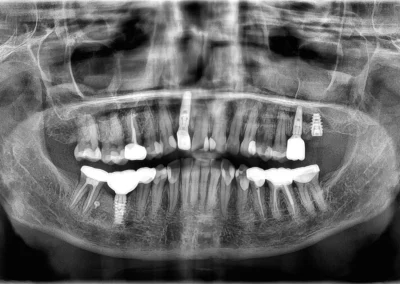

Implant Supported Dentures

Implant Overdenture Before and After